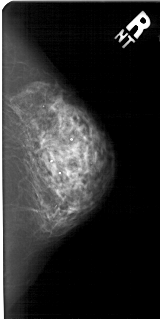

A_1510_1.RIGHT_MLO

RIGHT_MLO LINES 5491 PIXELS_PER_LINE 2761 BITS_PER_PIXEL 12 RESOLUTION 43.5 NON_OVERLAY